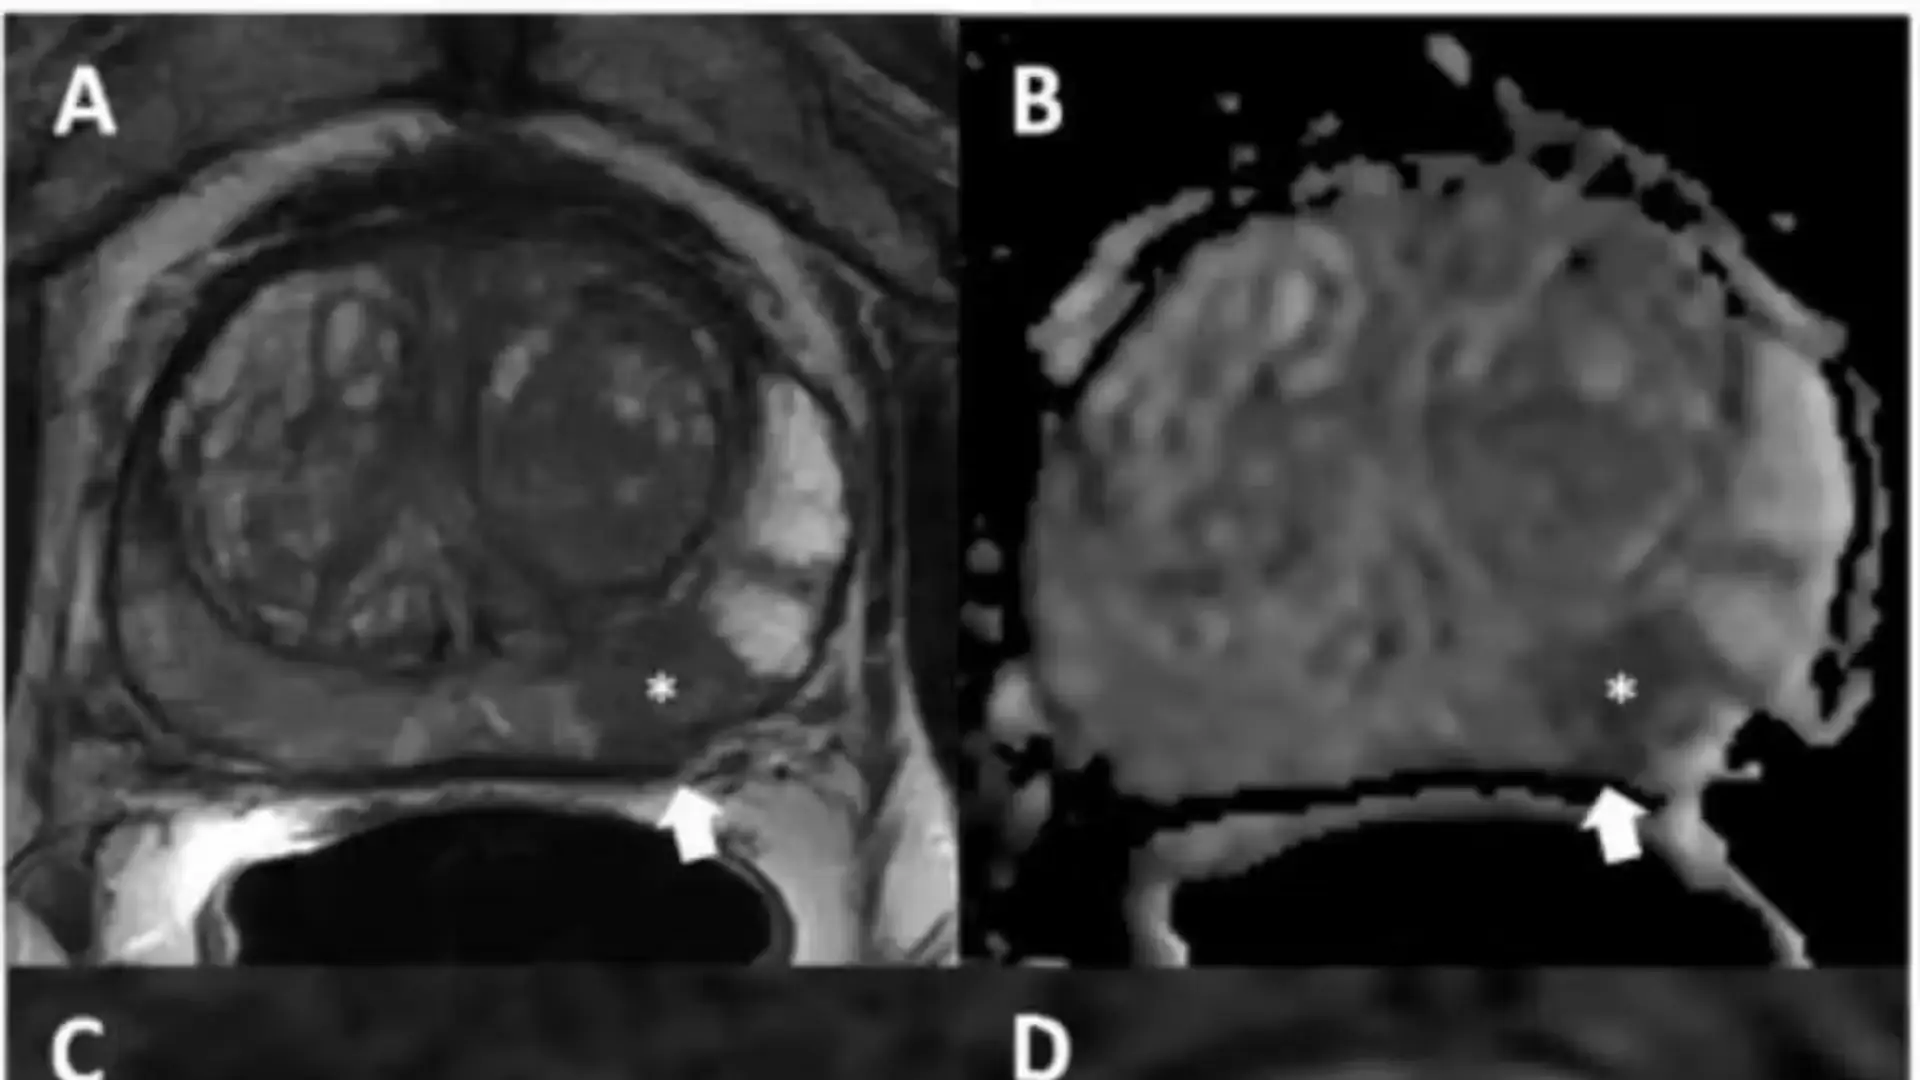

Los resultados del estudio publicado en Radiology demostraron mejoras importantes en el manejo del cáncer de próstata. Con la técnica de ablación con una sola fibra, se observó una reducción del 44 por ciento en los niveles de PSA, pasando de 6 ng/mL a 3.4 ng/mL, pero con una tasa de recurrencia del 49 por ciento, de la cual el 77 por ciento correspondió a recurrencias locales.

En contraste, la modalidad multifibra mostró una reducción del 65 por ciento en los niveles de PSA, de 8 ng/mL a 2.8 ng/mL, y una tasa de recurrencia significativamente menor, del 18 por ciento.

La alta resolución de la micro-ecografía y la planificación precisa mediante MRI permitieron delimitar con exactitud el área a tratar, garantizando un adecuado margen oncológico. Además, se constató que el procedimiento no afectó significativamente la calidad de vida ni la función urinaria de los pacientes, aunque se reportó una ligera disminución en el International Index of Erectile Function.

Un caso de fístula retroprostática destacó la necesidad de emplear medidas preventivas, como la hidrodesinfección rectoprostatica, especialmente en tumores localizados en zonas periféricas. Estos hallazgos resaltan el potencial de la técnica multifibra para ofrecer un tratamiento focalizado, seguro y eficaz en el manejo del cáncer de próstata localizado.